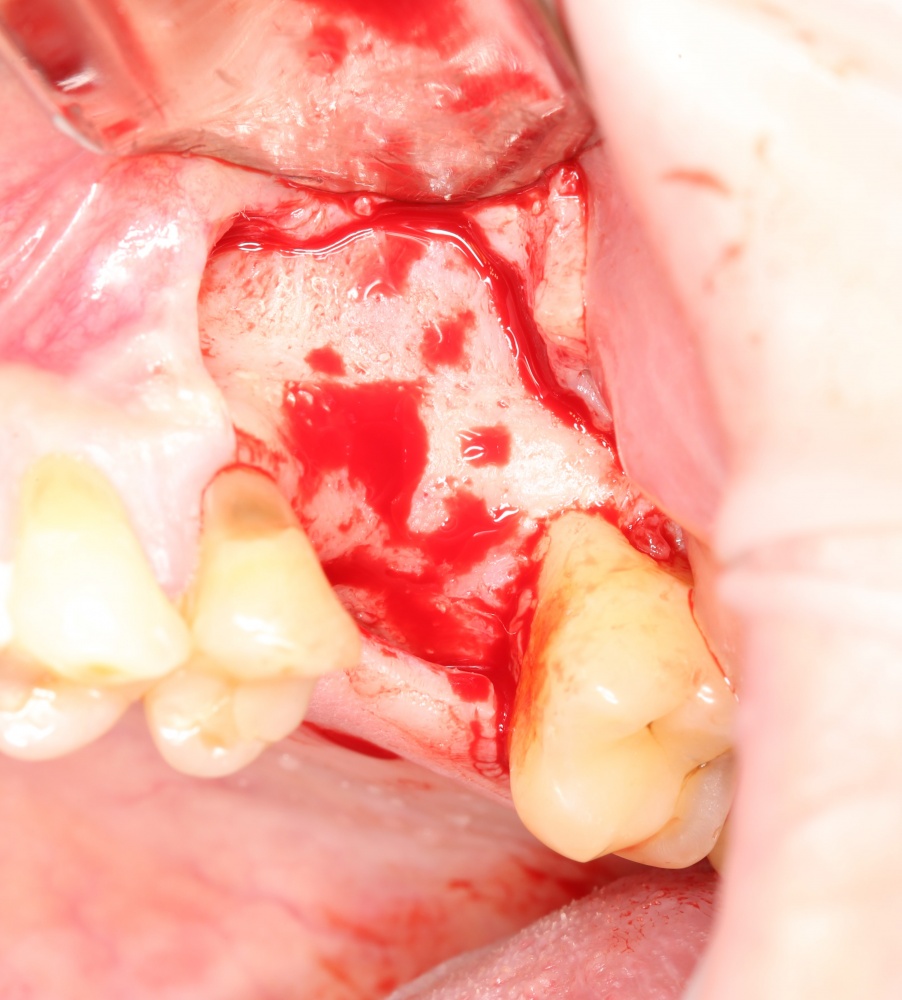

Простой синуслифтинг. Часть I.